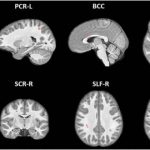

Study: Youth football changes nerve fibers in brain — (Details)

MRI scans show that repetitive blows to the head result in brain changes among youth football players, according to a new study being...